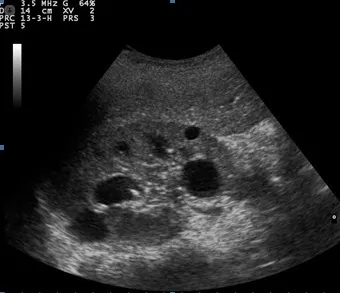

超聲波和基因檢測

超聲波:這種影像技術對於檢測腎臟中是否有囊腫非常有效。這是一種非侵入性方法,可以看到囊腫的大小、數量和位置。

超聱波檢查:定期超聲波檢查可用於評估囊腫發展和腎臟大小的變化。